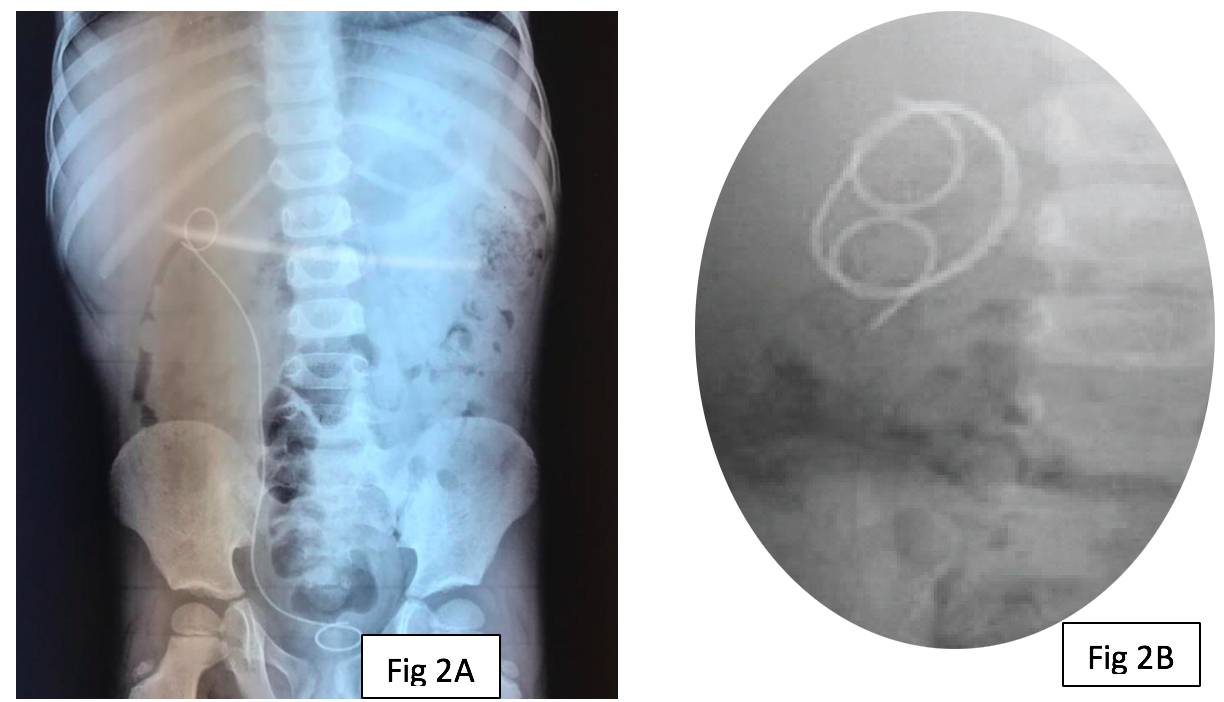

Case Series: Here we report proximal migration of DJ stent in three children with pelvi-ureteric junction (PUJ) obstruction treated with dismembered pyeloplasty. Ureteroscopy and retrieval of migrated DJ stents were performed in each of these patients.

Conclusion: Proximal migration of DJ stent, though rare, can cause significant morbidity and complicates it’s removal. Proper size and positioning of stent is required for pediatric patients.